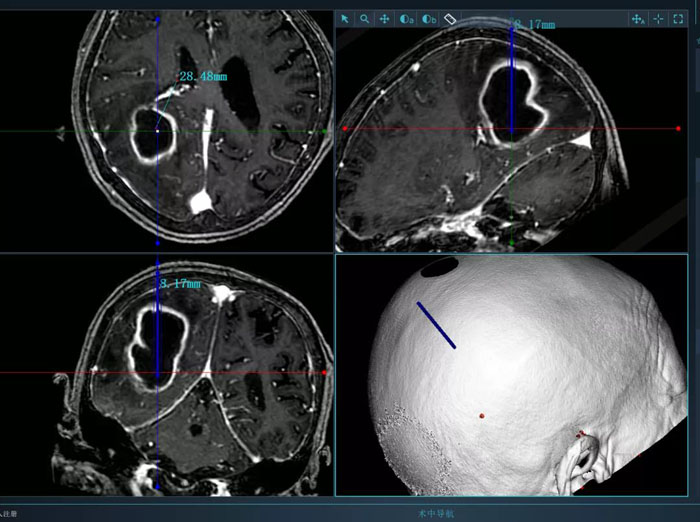

病例2.患者為74歲老年女性,術(shù)前因高熱入院,檢查發(fā)現(xiàn)腦膿腫。該患者體質(zhì)較差,而且膿腫體積大,形態(tài)不規(guī)則,傳統(tǒng)穿刺引流方式難以完全將膿腫引流徹底,且易造成膿腫擴散,引起嚴重不良后果。續(xù)繼軍主任決定采用智能機器人輔助穿刺,術(shù)前借助智能機器人手術(shù)計劃系統(tǒng)避開腦重要功能區(qū)及血管,精心設(shè)計了最優(yōu)穿刺路徑。續(xù)繼軍主任帶領(lǐng)丁鵬主治醫(yī)師在機器人引導下行膿腫穿刺引流,一次穿刺到位,術(shù)中引流出腦膿腫25ml。術(shù)后,復查CT顯示引流管到達預定靶點,位置良好,膿腫引流滿意,患者顱高壓癥狀明顯緩解,腦膿腫得到有效控制。